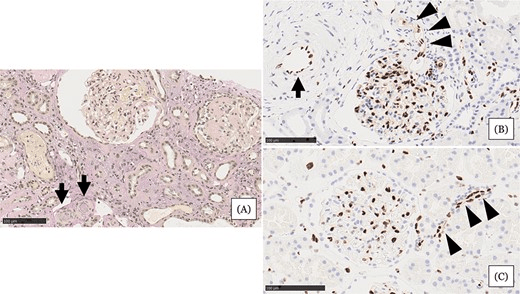

• 腎活檢示小動脈嚴重狹窄或阻塞,內(nèi)皮損害嚴重,腎小球萎縮,間質(zhì)細胞浸潤(圖1A)

• 與血壓正常的正常腎組織相比,血管內(nèi)皮細胞(EC)細胞核等長排列整齊(圖1C)

• 患者腎組織中EC細胞核大小不一,細胞核明顯,小動脈內(nèi)細胞核較少(圖1B)

綜合以上表現(xiàn),診斷該患者急性腎損傷類型為難治性高血壓合并微血管病性溶血導致的急性慢性缺血性腎損害。

圖1:住院第 31 天的腎臟活檢結(jié)果。